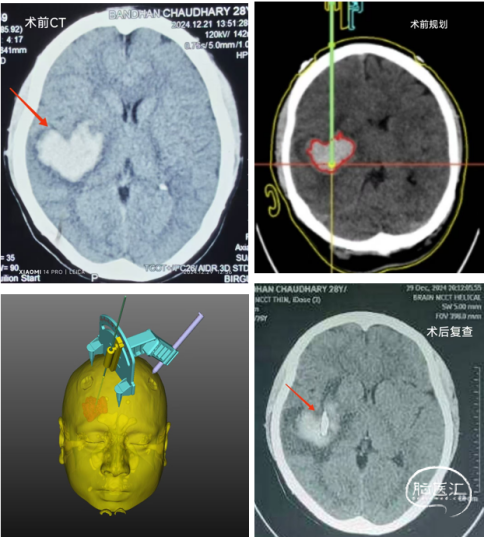

依次是術(shù)前CT的心形血腫,術(shù)前的平面規(guī)劃和手術(shù)設(shè)計,以及術(shù)后的CT復(fù)查,顯示引流管成為精準命中靶心的“丘比特之箭”